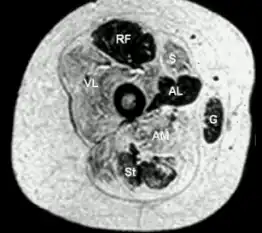

Transverse section from child with central core disease

Histopathologic appearance of typical central core disease: NADH-TR, transverse section from the rectus femoris. Marked predominance of dark staining, high oxidative type 1 fibres with cores affecting the majority of fibres. Cores are typically well demarcated and centrally located (→), but may occasionally be multiple and of eccentric location.